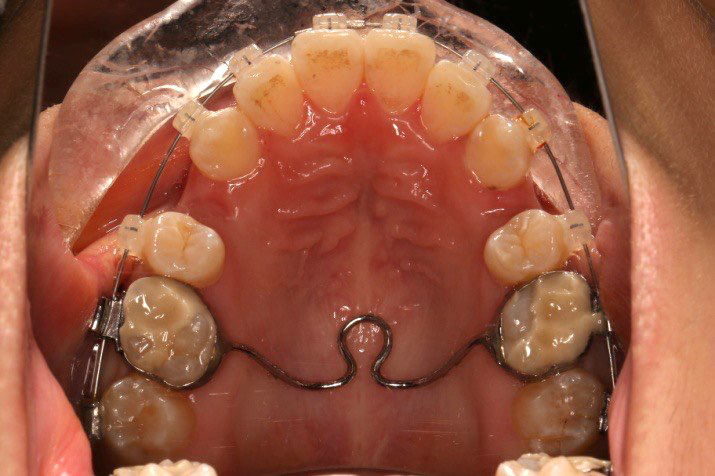

拔除14、24、34、44,上颌TPA+上颌高位支抗钉

1.第0个月:2016.10.31 ◆ 初戴,0.013cu-niti

2.第2.5个月:2017.1.13 ◆ 上颌加TPA,植入1312-08种植钉,上下0.16cu-niti

2016.10.31  初戴,0.013cu-niti2017.1.13  上颌加TPA,U56间斜形植入韩国庆北1312-08种植钉,上下0.16cu-niti

2017.02.16  上下0.014*25 cu-niti,50g 拉尖牙远中